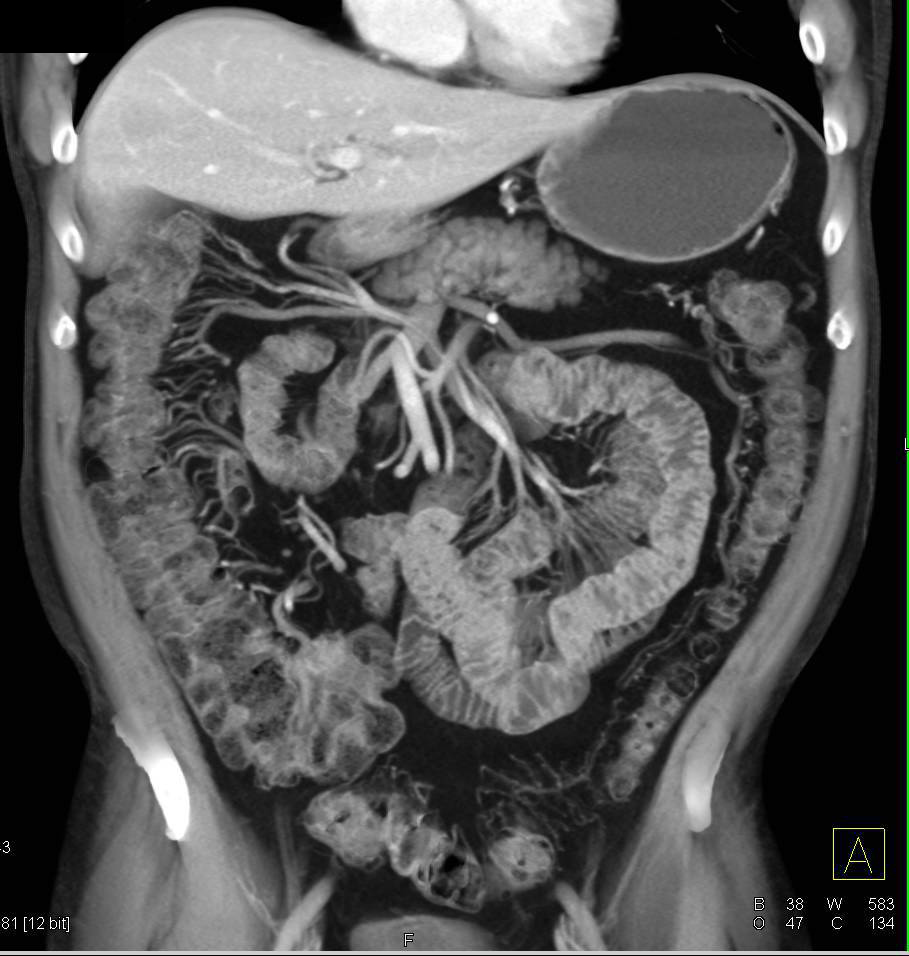

From www.ctisus.com

Lymphocytic Colitis with Nice Vasa Recta Small Bowel Case Studies Is There A Test For Lymphocytic Colitis Lymphocytic colitis is a form of. It leads to episodes of watery diarrhea and belly pain. Lymphocytic colitis is a cause of chronic diarrhea. It is a subtype of microscopic colitis characterized by chronic, watery, non‐bloody. Microscopic colitis, first described in 1980 [], has two main histologic subtypes, lymphocytic colitis, more specifically defined in. Gastroenterologists and pathologists are recognizing nonbloody. Is There A Test For Lymphocytic Colitis.